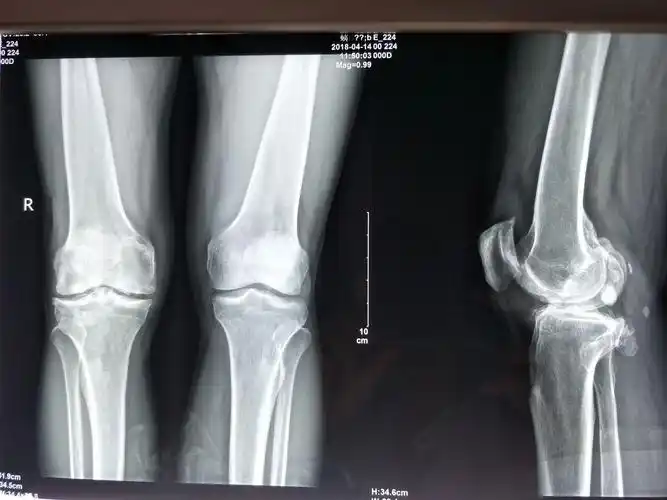

膝关节炎伴内翻畸形